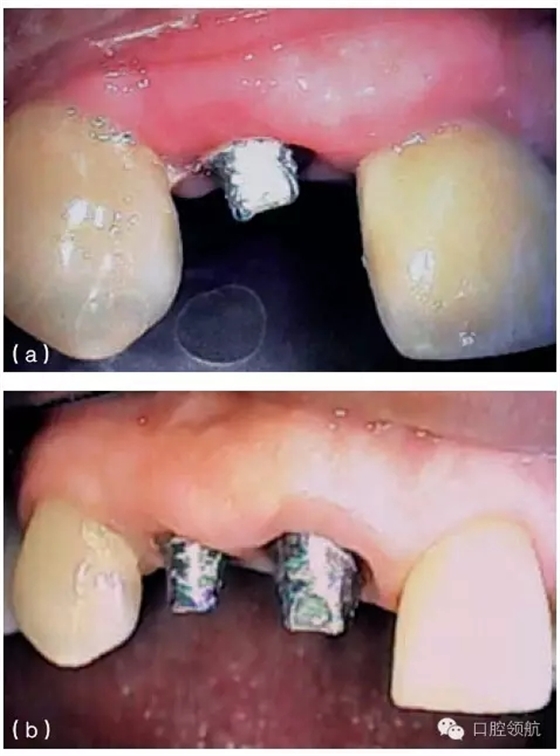

種植體周圍有一個淺的組織袖口,但這個袖口可能位于鄰近牙或種植體的根方。當(dāng)種植體植入時,牙槽嵴已經(jīng)發(fā)生垂直吸收,就會出現(xiàn)這種情況。當(dāng)種植體植入這些未行位點恢復(fù)的區(qū)域時,種植體跟鄰牙間的牙齦不在同一水平,這將造成不平整的牙齦形態(tài)。如果修復(fù)體在美學(xué)區(qū)域內(nèi),使用齦色瓷(或復(fù)合材料)可以部分遮蓋牙齦高度差異(圖9.24a,b)。另外,當(dāng)一個長的臨床牙冠可以被患者的嘴唇遮蓋時,這種方案也是可取的。因而,在制訂治療計劃的時期,就要考慮到是否存在不一致的骨水平。為了克服這些不一致的情況,獲得滿意的修復(fù)效果,使用CT檢查及外科模板,有利于評估預(yù)期修復(fù)體與缺失軟硬組織之間的

關(guān)系。如果這些不規(guī)則的差異,在美學(xué)方面不能讓患者滿意,醫(yī)生在診斷和進行外科手術(shù)之前,必須充分評估及討論缺失組織的再生潛力。

圖9.24 (a) 由于種植體植入前,沒有進行充分的位點恢復(fù),最終在修復(fù)體唇面輔以齦色瓷,以彌補軟組織的不足。(b)口內(nèi)全景觀,全口烤瓷熔附金屬修復(fù)體,粘結(jié)固位,注意左側(cè)側(cè)切牙牙齦區(qū)域的齦色瓷。